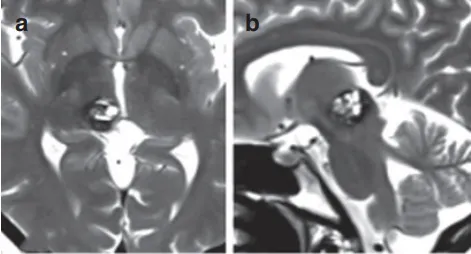

3岁女孩的脑干手术,竟然揭开了这个家庭的遗传秘密。 可爱的妮娜,突发脑干出血,嗜睡、头痛、右侧偏瘫(伴面瘫)以及言语障碍一切都因为脑干长了一个巨大的海绵状血管瘤,并且大脑里...